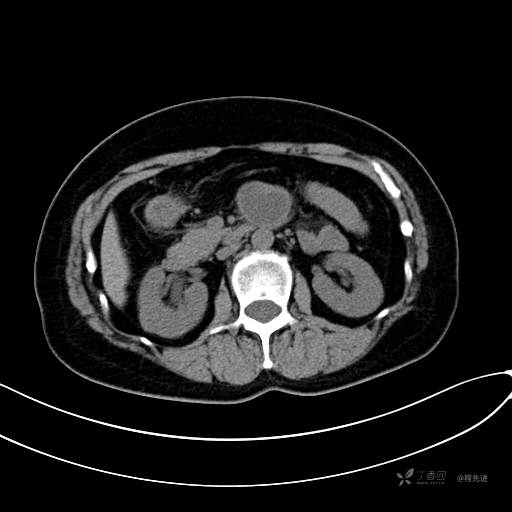

CT增强动脉期